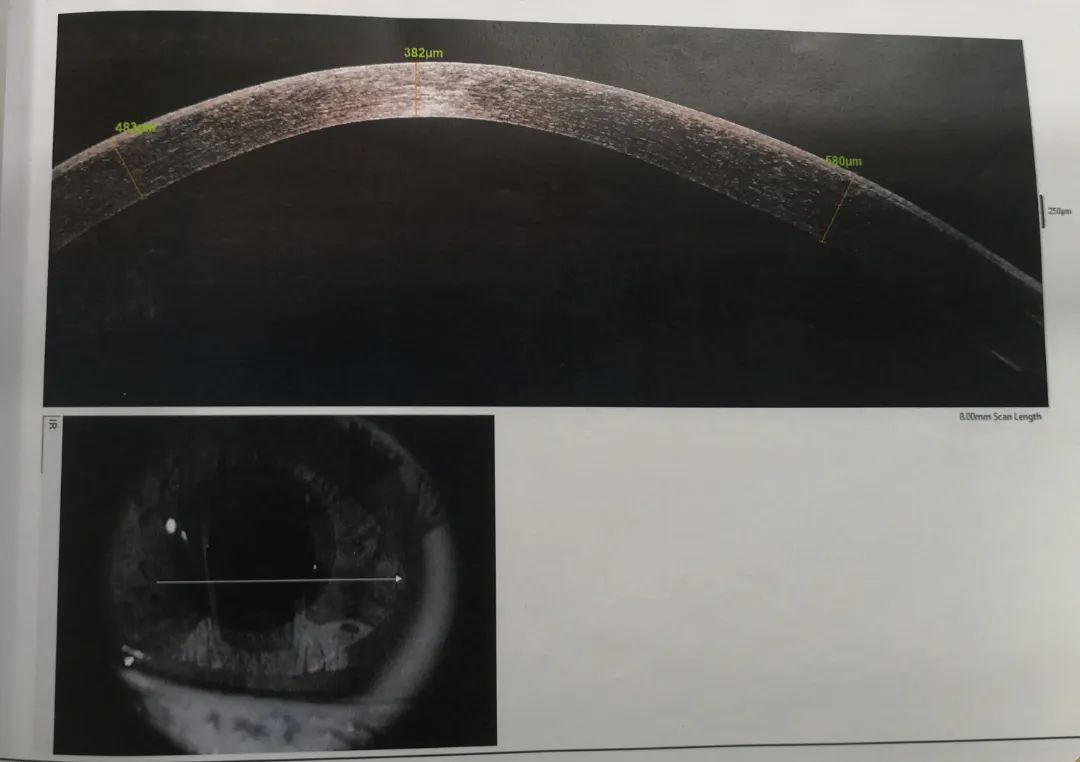

小雨重新回憶起之前的診治經(jīng)歷,確定此前的檢查中并沒(méi)有圓錐角膜的檢查,羅順榮副主任為她完善了相關(guān)檢查。檢查結果顯示,小雨左眼還是圓錐角膜初期,但右眼已經(jīng)是圓錐角膜的完成期,左眼角膜厚度為489μm,而右眼僅剩下382μm。

治療刻不容緩,羅順榮副主任建議小雨馬上進(jìn)行角膜交聯(lián)的手術(shù),通過(guò)手術(shù),增加角膜的強度,阻止圓錐角膜進(jìn)一步發(fā)展。